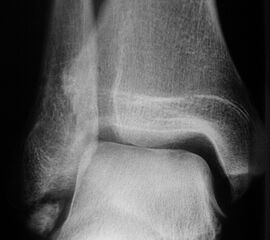

Sprunggelenk lateral ohne Belastung

Positionierung:

• Patient liegt auf dem Rücken und dreht den Fuß des aufzunehmenden Beins so nach innen, dass beide Malleolen genau übereinanderstehen.

• Die laterale Fuss-Seite liegt auf der Kassette, das Sprunggelenk ist 90° angewinkelt.

• Der Zentralstrahl wird zentral auf das Sprunggelenk gerichtet.

Kennzeichen des Röntgenbildes:

• Oberes und unteres Sprunggelenk sind rein seitlich abgebildet, inklusive Kalkaneus.

• Die Malleolen kommen übereinander zu liegen.

• Tibiagelenkfläche und Talusrolle werden exakt seitlich dargestellt, es kommt zu keinen Doppelkonturen.

• Die Fibula projiziert sich ins mittlere bis hintere Drittel der Tibiagelenkfläche.

• Die vordere und hintere Tibiakante, das Chopart-Gelenk und das Subtalargelenk kommen zur Darstellung.

• Das proximale Ende des Os metatarsale V ist mit abgebildet.

• Der Weichteilmantel (Achillessehne) ist erkennbar.

Besondere Bemerkungen zum Beispielbild:

• Patient mit anamnestisch chronischer OSG Instabilität.

• Ventral der Tibia findet sich ein abgebrochener Osteophyt.

Zur Vollansicht und zum Lesen der Bildbeschreibung bitte die Bilder anklicken.